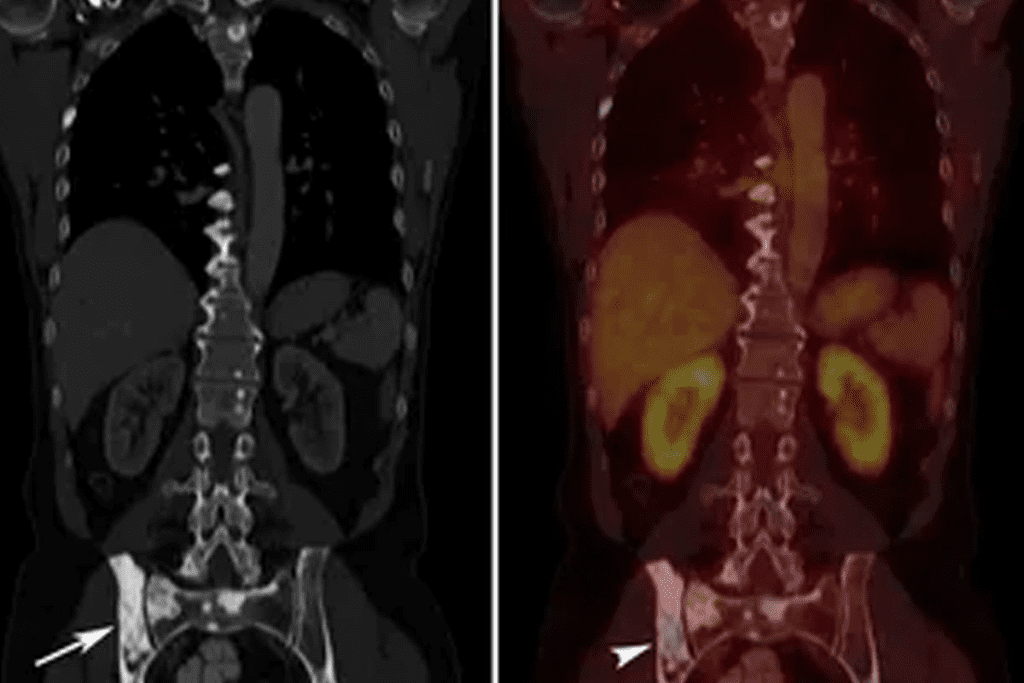

Interpreting PET Scan Images: The Color Spectrum

Understanding PET scan images means knowing the color scale. This scale shows how active different body parts are. It’s key for spotting and tracking health issues.

Understanding the Standard Color Scale

The PET scan color scale goes from black and blue to red and white. Black and blue mean low activity, while red and white mean high activity. This helps find out if parts of the body are working right or not.

Colors are very important in reading PET scans. For example, bright spots on the scan often mean cancer. This is because cancer cells take up more glucose.

Metabolic Activity and Color Representation

Metabolic activity is shown through colors. Hotter colors like red and white mean high activity. Cooler colors like blue and black mean low activity. This color system is key for checking the health of tissues and organs.

What Do Black Spots on a PET Scan Mean?

PET scan images often show black spots. These can mean different things, from normal body parts to serious health issues. It’s important to understand what these spots mean for the right diagnosis and treatment.

Normal Anatomical Structures That Appear Black

Pathological Causes of Black Areas

But some black spots are not okay. They can show serious health problems. These include:

- Cystic lesions or fluid-filled structures that don’t take in the tracer, showing up as black.

- Necrotic tissue in tumors, which looks black because it’s not active.

- Certain types of tumors or metastases don’t show much activity, appearing as black spots.

Differential Diagnosis of Black Regions

Figuring out what black spots mean on a PET scan is complex. Doctors must look at both normal body parts and possible health issues. They need to:

- Match PET scan results with other scans like CT or MRI.

- Think about the patient’s medical history and symptoms.

- Look at how the black spots are spread to guess what they might be.

Getting black spots on a PET scan right means looking at the scan’s tech and the patient’s health together.